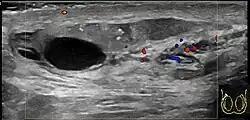

Doppler ultrasound of epididymitis, seen as a substantial increase in blood flow in the left epididymis (top image), while it is normal in the right (bottom image). The thickness of the epididymis (between yellow crosses) is only slightly increased.

Epididymitis usually has a gradual onset. Typical findings are redness, warmth, and swelling of the scrotum, with tenderness behind the testicle, away from the middle (this is the normal position of the epididymis relative to the testicle). The cremasteric reflex (elevation of the testicle in response to stroking the upper inner thigh) remains normal.[1] This is a useful sign to distinguish it from testicular torsion. If there is pain relieved by elevation of the testicle, this is called Prehn's sign, which is, however, non-specific and is not useful for diagnosis.[13] Before the advent of sophisticated medical imaging techniques, surgical exploration was the standard of care. Today, Doppler ultrasound is a common test: it can demonstrate areas of blood flow and can distinguish clearly between epididymitis and torsion. However, as torsion and other sources of testicular pain can often be determined by palpation alone, some studies have suggested that the only real benefit of an ultrasound is to assure the person that they do not have testicular cancer.[14]: p.237  Nuclear testicular blood flow testing is rarely used.